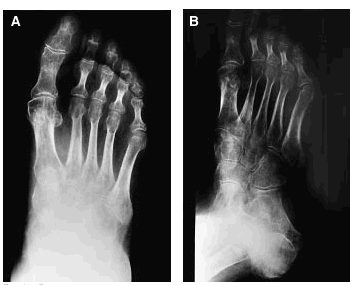

Se trata de una paciente de 58 años de edad, con antecedentes de osteoporosis, que tras sufrir una caída se practicó unas radiografías (figs. 1A y B) donde le encontraron una fractura de la falange proximal del primer dedo del pie derecho y un esguince de tobillo, por lo que le pusieron un tratamiento sintomático con lo que fue empeorando de su cuadro doloroso con limitación funcional, hasta 3 meses más tarde en que se practica una nueva radiografía (figs. 2A y B), donde se confirma una osteoporosis difusa con imágenes líticas, preferentemente en la articulación tibio-peroneo-astragalina, así como en calcáneo.

Figs. 2A y B

Sigue tratamiento con antiinflamatorios sin mejoría, hasta su visita a nuestro Servicio, 7 meses después de su caída. En la exploración de pie derecho se confirma edema duro de piel, limitación en la movilidad activa y pasiva, sin signos de participación vascular. Se practicó un eco-doppler venoso donde se aprecia una insuficiencia del tercio distal de la safena sin evidencia de tromboflebitis y una nueva radiografía (figs. 3A y B), donde las lesiones anteriormente descritas se han hecho aún más llamativas.

Figs. 3A y B